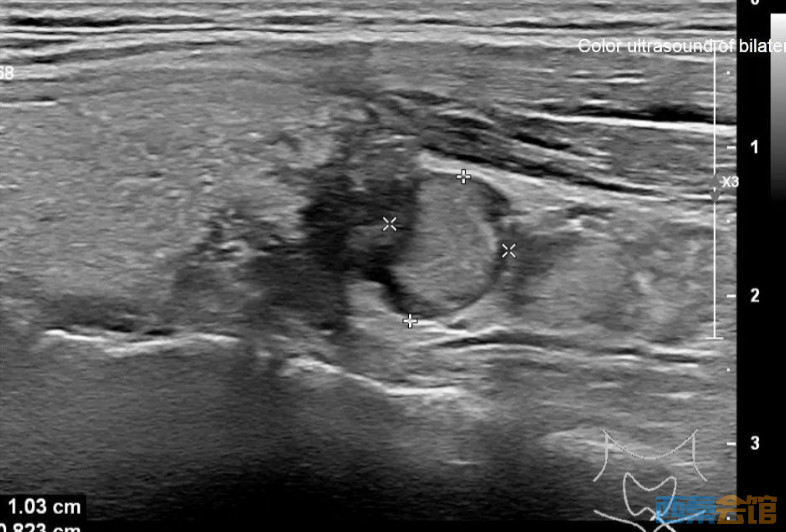

接着,医生安排她做超声波检查,结果显示她的甲状腺左叶有一个2.5公分大的结节、左侧颈部还有一个1公分大的淋巴结。

图:甲状腺结节

根据结节的形态和大小,医生决定进一步进行细针穿刺活检,以排除恶性肿瘤的可能性。不幸的是,活检结果显示结节是恶性的——甲状腺乳头状癌。